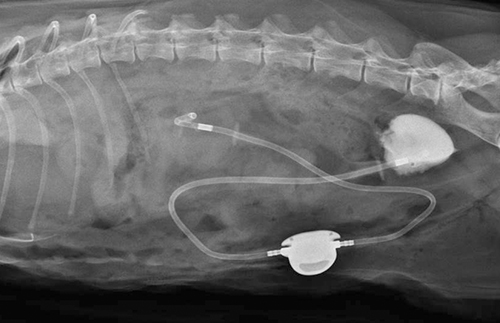

- 외과센터 소개 - 외과수술 종류 - 주요수술 안내